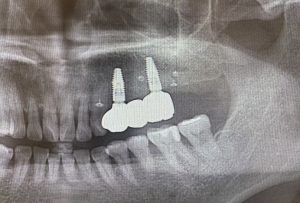

治療後レントゲン

人工骨を用いて骨造成を行ったため、レントゲンで白く映る骨ができている。